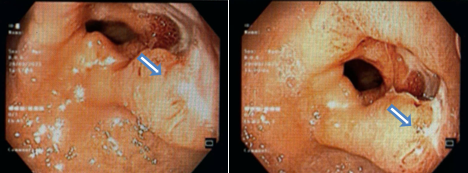

+ Nội soi Thực quản-dạ dày-hành tá tràng: Tiền môn vị có ổ loét kích thước 2cm, niêm mạc phù nề xung huyết, đáy phủ giả mạc

Hình 1. Hình ảnh nội soi dạ dày-Thực quản: Tiền môn vị có ổ loét kích thước 2cm, niêm mạc phù nề xung huyết (mũi tên xanh)

Hình 2. Hình ảnh nội soi: Khối sùi đáy có giả mạc trắng (mũi tên xanh)

+ Siêu âm nội soi gây mê dạ dày: Tổn thương sùi lỗ môn vị chiếm hết ½ chu vi môn vị có cấu trúc giảm âm không đều. Chỗ dày đo được 1,1 cm. Tổn thương lan tới lớp thanh mạc thành môn vi. Gần tổn thương phía bờ cong nhỏ có hạch giảm âm kích thước 0.8 cm